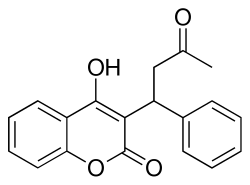

Chemistry

X-ray crystallographic studies of warfarin show that it exists in tautomeric form, as the cyclic hemiketal, which is formed from the 4-hydroxycoumarin and the ketone in the 3-position substituent.[79] However, the existence of many 4-hydroxycoumadin anticoagulants (for example phenprocoumon) that possess no ketone group in the 3-substituent to form such a structure, suggests that the hemiketal must tautomerise to the 4-hydroxy form in order for warfarin to be active.[80]